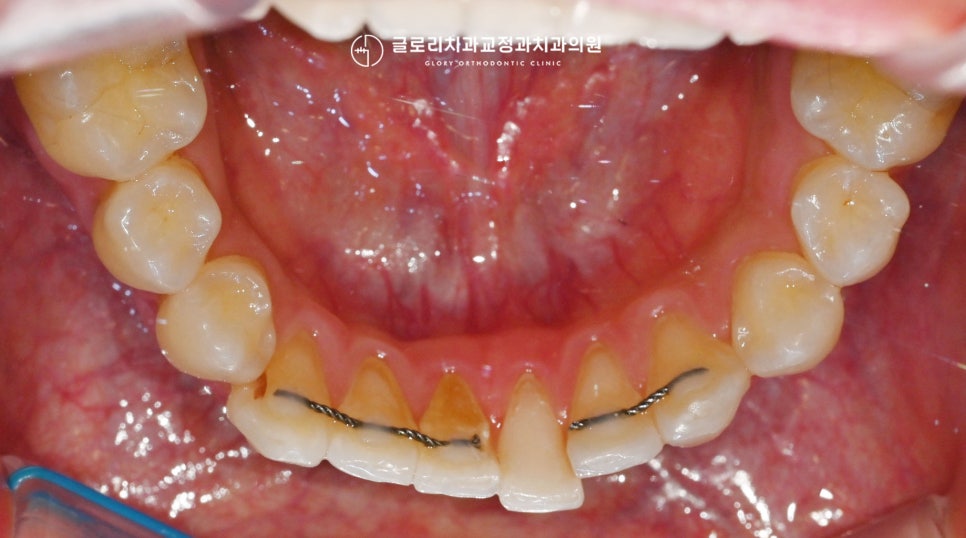

현재 전치부 뒤쪽으로는 이렇게

유지 장치를 부착해두셨는데요.

부착한 이후에 한 번의 철사 끊어짐이 있어

일부는 연결하지 않은 채

사용을 이어가고 계셨습니다.

정면에서 보았을 때 전체 배열에 대한 문제보다는

부분적으로 개선할 곳들이 있었는데요.

완료를 하신 이후에 한동안은 잘 몰랐으나

시간이 지나니 점점 이곳들만

눈에 띄어 거슬리게 되었다고 하셨습니다.